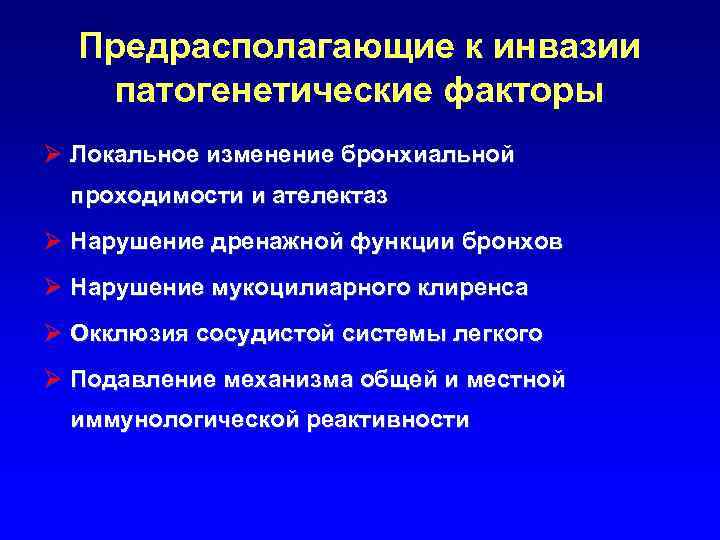

Предрасполагающие к инвазии патогенетические факторы Ø Локальное изменение бронхиальной проходимости и ателектаз Ø Нарушение дренажной функции бронхов Ø Нарушение мукоцилиарного клиренса Ø Окклюзия сосудистой системы легкого Ø Подавление механизма общей и местной иммунологической реактивности